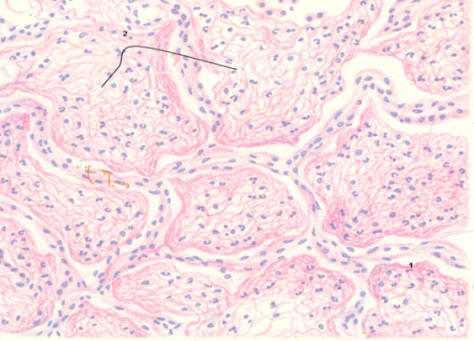

Карнификация Легкого: Микропрепараты и Диагностика

Раздел: Калейдоскоп образов